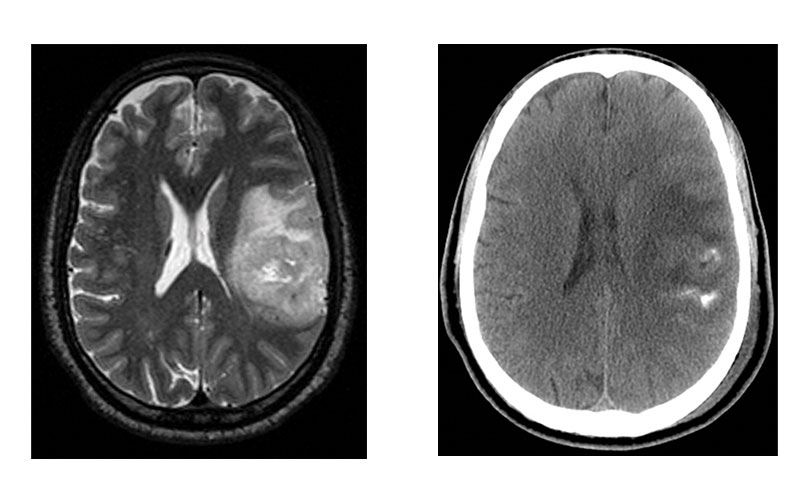

Images in representative case of disagreement between neuroradiologist and fluorescence in situ hybridization (FISH) classification in a 53-year-old man with an isocitrate dehydrogenase–mutant lower-grade glioma. (a) Axial image from T2-weighted MRI shows a left frontoparietal mass with marked internal heterogeneity and extensive cortical infiltration. (b) Axial noncontrast CT scan shows calcifications associated with the mass. On the basis of the imaging findings, the consensus neuroradiologist prediction for 1p/19q was “codeleted.” (c) FISH showed no evidence of 1p/19q codeletion. (d) Chromosomal (Chr) microarray analysis showed 1p/19q codeletion (arrows), as well as trisomy for chromosome 9 (*).

Sohil et al Radiology 2020; 294:160–167 ©RSNA 2020